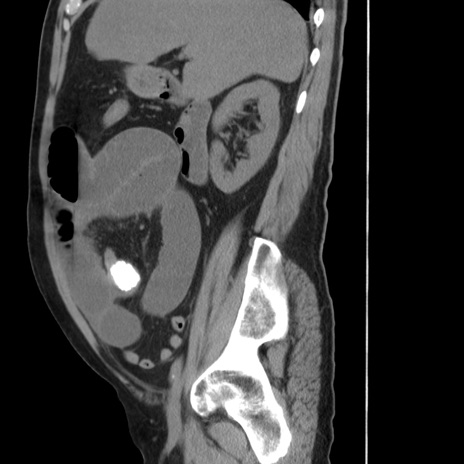

冠状断像

【症例】 60歳代男性

【主訴】 腹部膨満、嘔吐

【現病歴】5日前頃より倦怠感を認め食事量減少し4日前の朝嘔吐、食事摂取困難となった。 3日前近医受診し点滴施行され整腸剤などを処方された。 当日他院を受診し、腹部膨満著明、炎症反応の上昇(CRP10.8、WBC11200)あり、紹介受診となる。

【身体所見】 意識JCS1 受け答えがはっきりしないBP 111/57mHg、 P 67bpm、、BT35.2°C、SpO2 97%(RA)、 腹部:膨隆、打診で鼓音あり、全体的に圧痛有り、腸蠕動音(-)、反跳痛ははっきりせず。

【データ】WBC 11400、CRP 14.20